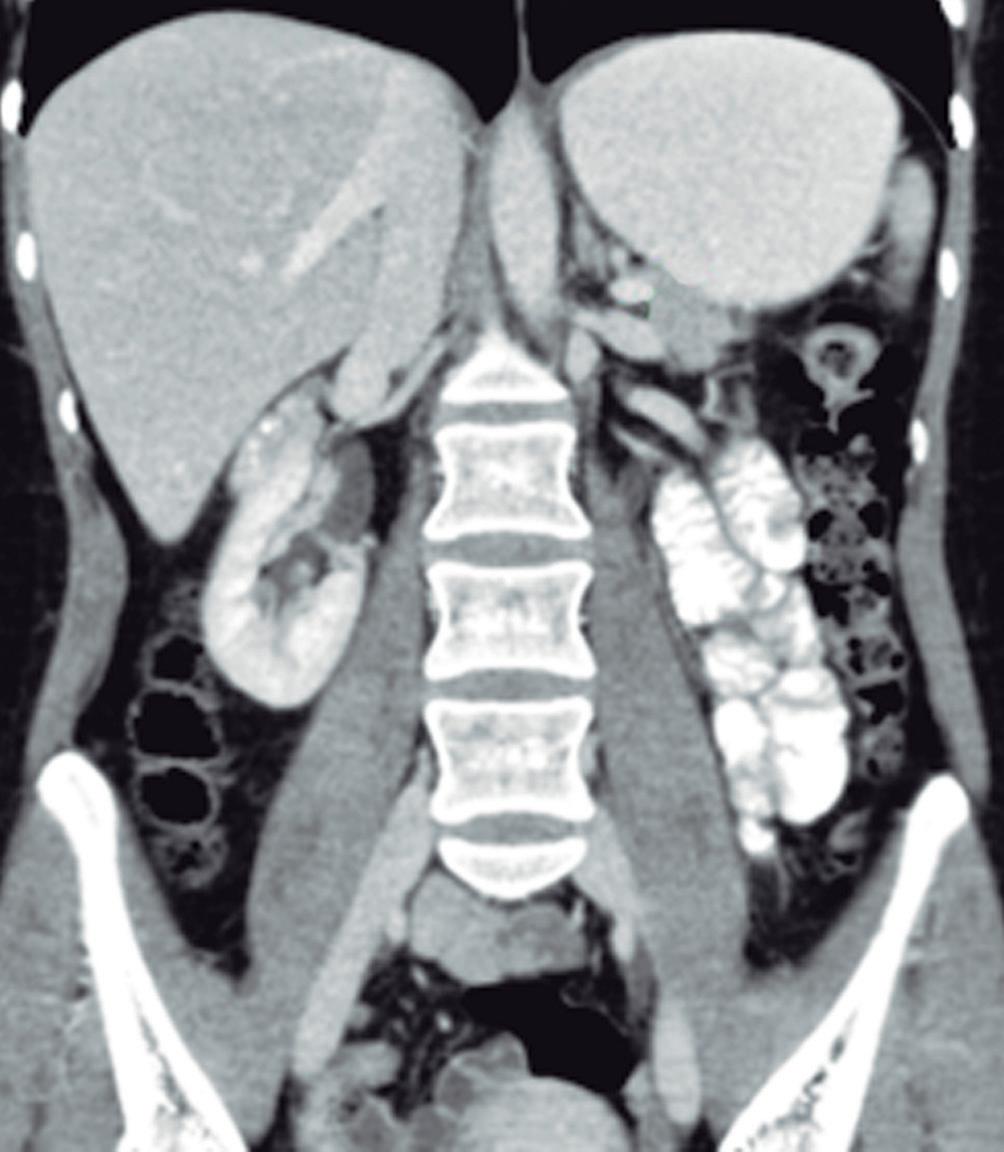

Evaluación de la dinámica de apertura de la unión esofagogástrica

Una fortaleza clave de la planimetría FLIP es su capacidad para cuantificar la dinámica de apertura de la UEG. Las métricas manométricas tradicionales, como la presión integrada de relajación (IRP), infieren la relajación de la UEG basándose en la presión intraluminal durante la deglución. En contraste, la FLIP mide directamente la apertura mecánica de la UEG bajo distensión, integrando de forma simultánea los efectos del tono del esfínter esofágico inferior, la función del diafragma crural y la complacencia de la pared esofágica.

La apertura de la UEG se evalúa mediante dos parámetros principales: el índice de distensibilidad de la UEG (DI-UEG), calculado como el área transversal mínima dividida por la presión intrabalón, y el diámetro máximo de la UEG alcanzado durante la distensión. Estas métricas han sido validadas frente al esofagograma baritado cronometrado y en relación con resultados clínicos, demostrando asociaciones sólidas con la obstrucción clínicamente relevante.9, 11

Según los umbrales establecidos, la apertura de la UEG puede categorizarse como normal, limítrofe o reducida. La apertura normal se define por un DI-UEG ≥ 2,0 mm²/mmHg con un diámetro máximo ≥ 16 mm, mientras que la apertura reducida se define por un DIUEG < 2,0 mm²/mmHg con un diámetro máximo < 12 mm. La apertura limítrofe incluye valores intermedios que no cumplen criterios para ninguna de las dos categorías.12

Es fundamental interpretar la apertura de la UEG en el contexto de la respuesta contráctil esofágica. Una UEG mecánicamente adecuada puede, no obstante, generar obstrucción funcional del tránsito del bolo en pacientes con peristalsis ausente o gravemente deteriorada, lo que subraya la necesidad de una interpretación integrada y contextualizada, en lugar de basarse en métricas aisladas.

Durante la planimetría FLIP, un catéter con balón complaciente que contiene múltiples electrodos de impedancia y un transductor de presión se posiciona atravesando la unión esofagogástrica (UEG). La distensión escalonada o sostenida del balón (habitualmente 4070 mL) genera una deformación luminal que permite la medición simultánea del área transversal y la presión intrabalón a lo largo del eje esofágico. Los datos se representan como mapas espaciotemporales de diámetro, proporcionando una visualización en tiempo real de la apertura de la UEG y de la actividad contráctil del cuerpo esofágico.12